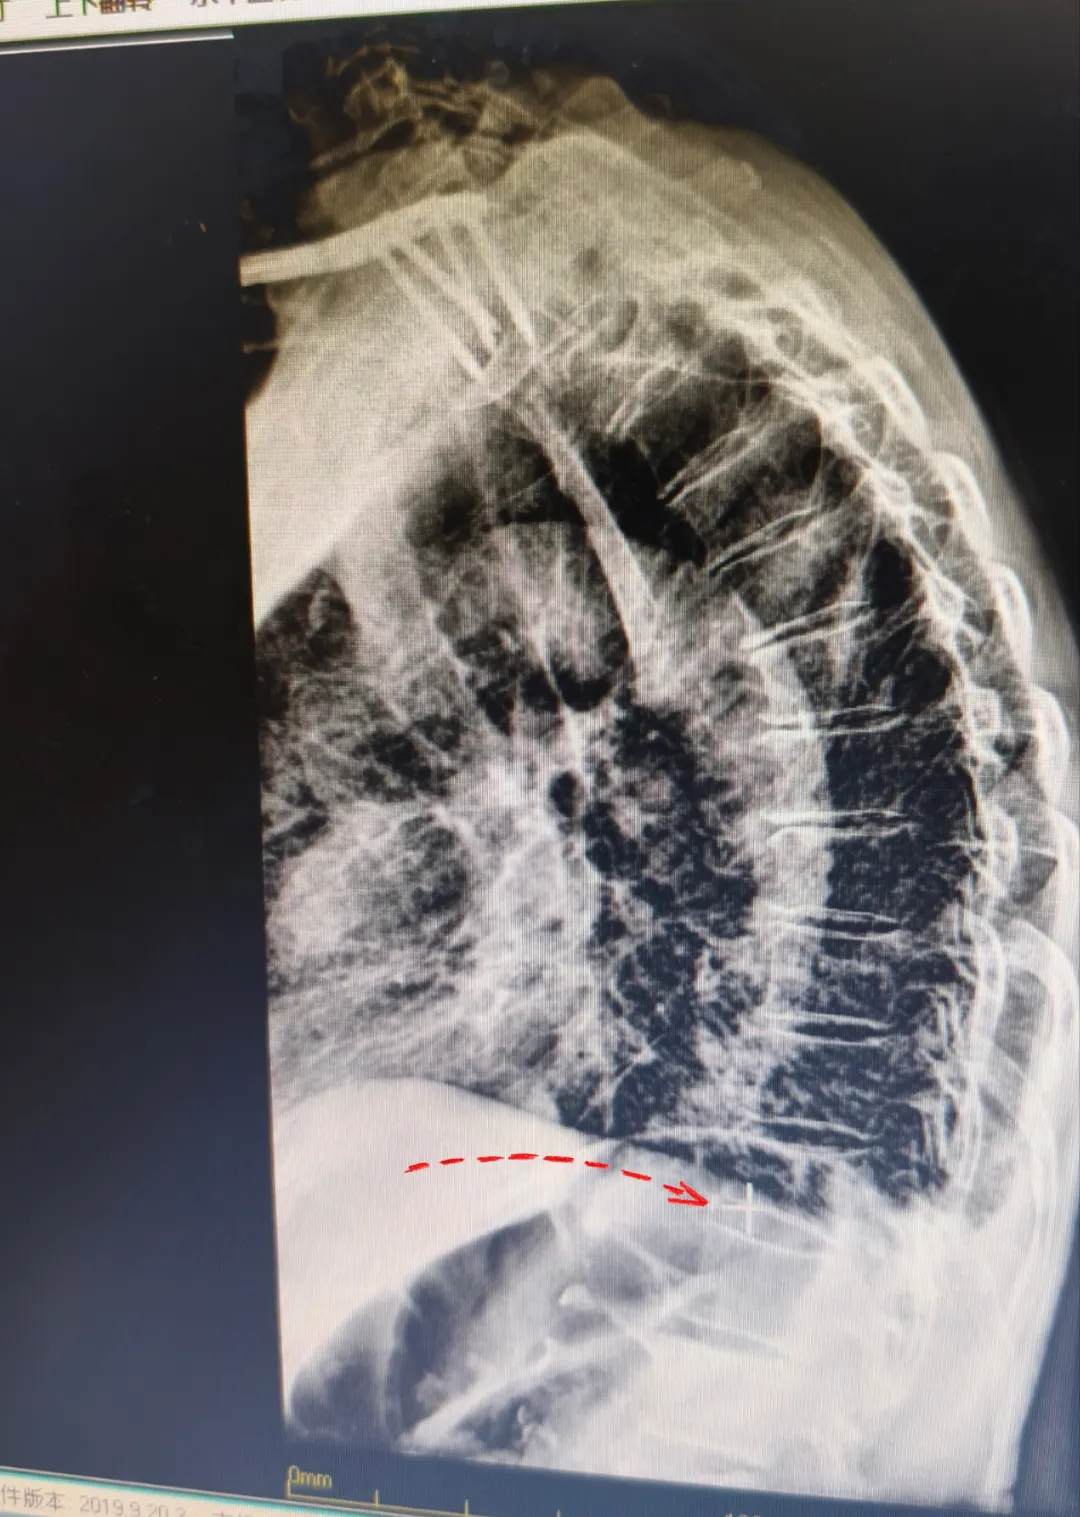

目前脊柱椎體成形手術(shù)是針對骨質(zhì)疏松所致的壓縮性骨折,椎體腫瘤等椎體壓縮性或病理性骨折所做的一種微創(chuàng)手術(shù)。椎體成形術(shù)對患者的疼痛緩解率較高,許多患者備受腰酸背痛的困擾,在手術(shù)后很快就感覺到疼痛的明顯緩解,手術(shù)在局麻下進(jìn)行,創(chuàng)傷小、安全性高,術(shù)后數(shù)小時(shí)即可下地活動,有效避免了術(shù)后可能發(fā)生的神志障礙,也避免了因長期臥床引起的褥瘡、肺炎等并發(fā)癥,尤其適合于老年患者。